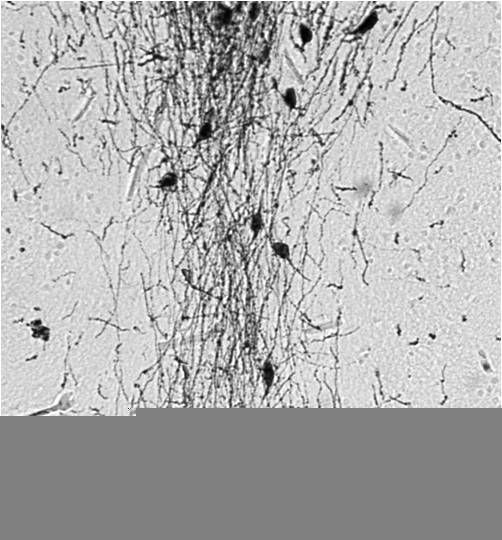

Supportive validation

- Submitted by

- GeneTex (provider)

- Main image

- Experimental details

- HC analysis of mouse embryonic brain using GnRH antibody.

- IHC analysis of Hyla cinerea (green treefrog) forebrain using GnRH antibody at a dilution of 1:1000.